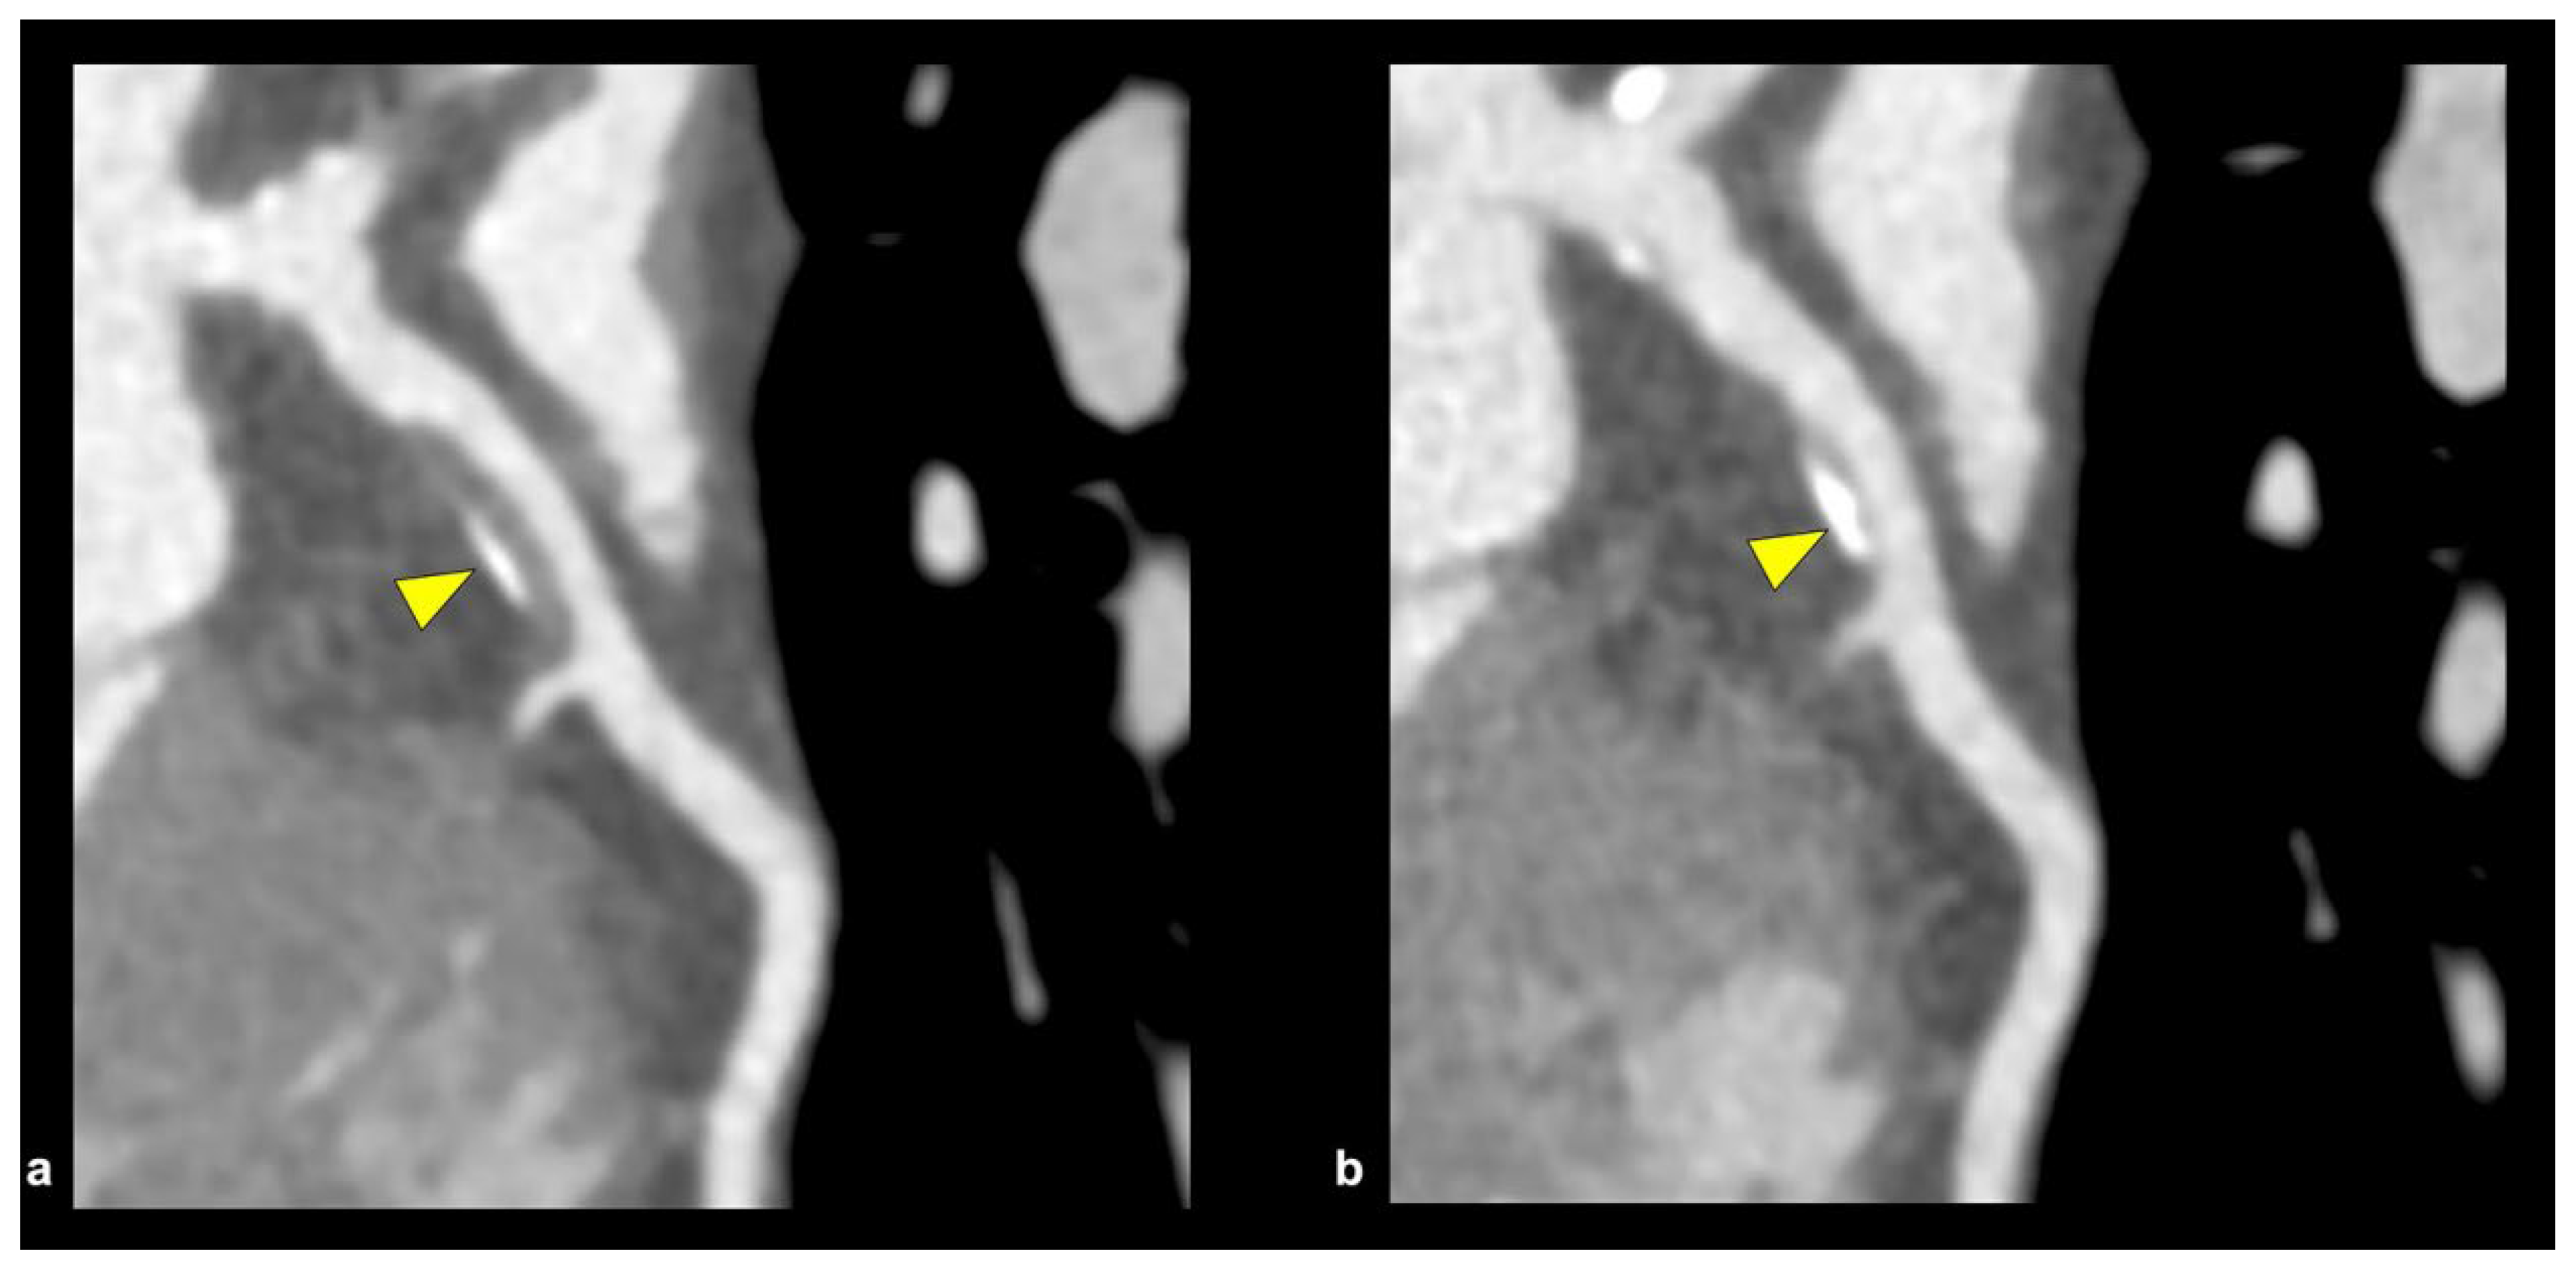

The effective execution and operation of intracoronary imaging modalities during these procedures improve both procedural and long-term clinical outcomes, particularly in intravascular ultrasound (IVUS) (Figure 6 and Figure 7) and optical coherence tomography (OCT) (Figure 8 and Figure 9), where coronary lesion morphology and mapping facilitate better PCI procedural planning [46]. Both IVUS and OCT can detect, localize, and quantify coronary calcification. Notably, OCT can visualize the calcified plaque without producing visual imaging artifacts, thereby minimizing observational scatter, and can evaluate calcium thickness more accurately than IVUS.

Intravascular ultrasound (IVUS) can provide information related to the arc, length, and superficial/deep texture of calcified plaques, but is restricted to the higher capabilities and superiority of optical coherence tomography (OCT), which can provide more than 10 times the spatial resolution of calcium deposits in the coronary walls when compared to the former imaging modality [33]. Both OCT and IVUS have demonstrated that CNs frequently present as eccentric, protruding calcific deposits disrupting luminal geometry. This morphology is associated with difficult wire passage, balloon slippage, and high rates of incomplete stent expansion, all of which translate into increased procedural complexity and suboptimal clinical outcomes [34,35].